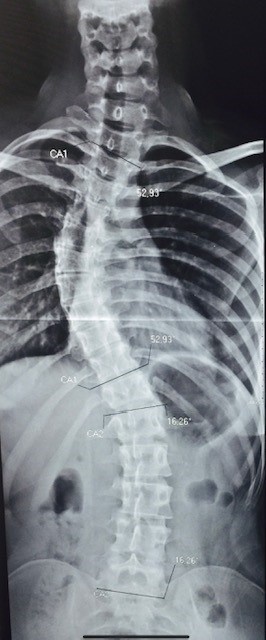

- Radiografia panorâmica da coluna com escoliose

Radiografia panorâmica da coluna

Com escoliose torácica de 50